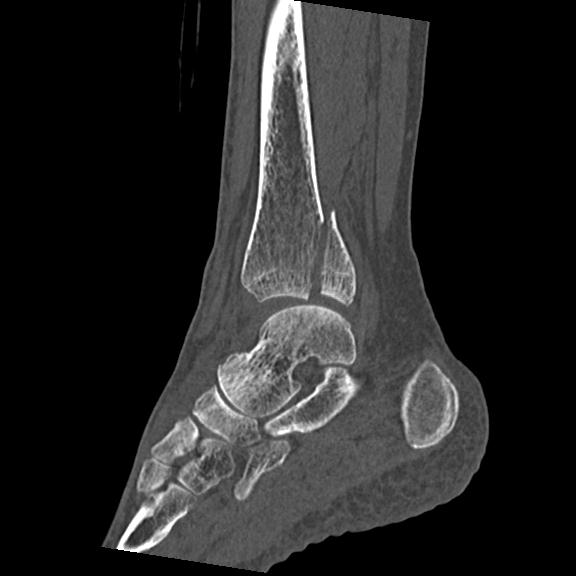

102755 1/4 2R 1/15 2R 右足関節 68歳女性 右三果脱臼骨折